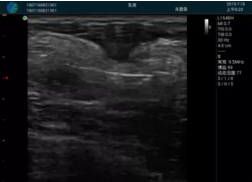

清晰顯示孕囊,通過(guò)軟件包計(jì)算孕齡7w+6d

M20實(shí)時(shí)引導(dǎo),術(shù)中清晰顯示孕囊被破壞和抽吸針的過(guò)程,清晰顯示吸引針

抽吸結(jié)束后縱切子宮,孕囊已被完全抽吸,未見(jiàn)明顯殘留

橫切子宮,發(fā)現(xiàn)右側(cè)宮腔靠近宮角處有少許脫模樣殘留

M20引導(dǎo)下,抽吸針找到右側(cè)宮角處再次清掃

二次抽吸后再次進(jìn)行超聲檢查,宮腔未見(jiàn)殘留,宮腔線清晰顯示